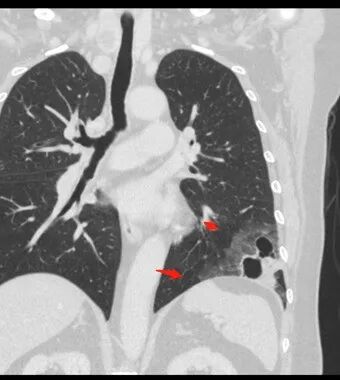

4、冠状位部分层面可见支气管在囊腔边缘截断。

胸CT:左肺下叶囊腔,壁厚薄不均,可见壁结节,囊腔内可见断裂小梁,部分融合,周围边界较清楚GGO,胸膜牵拉,可见血管集束、支气管充气征,冠状位部分层面可见支气管在囊腔边缘截断。考虑:囊腔型腺Ca。鉴别:肺大疱感染,CPAM等。

1、左肺下叶外基底段不规则囊腔样病灶,囊腔内有条形影及血管穿行。

2、囊壁薄厚不均匀,稍显僵硬,有壁结节(对应边缘分叶等)、结节强化明显。

以上两条几乎将肺囊肿彻底排除在外,且高度怀疑新生物!

3、灶周环以大范围磨玻璃影,非常均匀,没有重力分布趋势,分叶状,边界隐约可变。